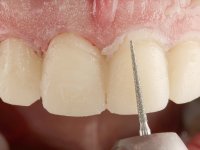

Realizado o diagnóstico e tomada a decisão quanto ao tratamento a executar, tornou-se importante definir qual a sequência de trabalho a adotar no sentido de conseguir a reabilitação da D.V.O. (V.D.O), de forma progressiva e equilibrada. Na primeira fase fez-se uma pré-impressão da arcada inferior com silicone tipo “putty” e em seguida realizou-se o preparo dentário de todo o sector posterior. O preparo para os overlays foi feito coronalmente à linha amelo cementaria no sentido de ser o mais conservador possível. A impressão foi feita com técnica de dupla mistura após afastamento gengival realizado com pasta de caulino. A provisória foi realizada com resina composta de polimerização dual. Em laboratório foram realizados os overlays após se ter aberto ligeiramente (1,5mm) a D.V.O. nos modelos montados em articulador semi-ajustável. Simultaneamente o sector antero-inferior foi encerado no sentido de acompanhar este aumento da D.V.O. Também foi confecionada uma chave de silicone translucido para posterior confeção dos provisórios antero-inferiores. Em boca foi primeiro realizada a provisionalização dos dentes anteriores utilizando resina composta previamente aquecida após preparação das superfícies dentárias para a adesão. Foi colocado o dique de borracha para promover o isolamento absoluto e posteriormente foram colados os overlays. Em laboratório foi realizada nova chave de silicone para confecionar os provisórios antero-superiores. Seguidamente em boca foram preparados os seis dentes antero-superiores após colocação do fio de afastamento gengival. Feita a preparação adequada das superfícies dentárias foi realizada a impressão com técnica de dupla mistura e a respetiva provisória. Em laboratório foram confecionadas 6 facetas feldespáticas num modelo de trabalho tipo “Geller”. A provisória foi removida e as facetas foram coladas em boca utilizando um isolamento relativo competente. Esta opção foi tomada em virtude de uma prévia experiencia negativa com a colocação do dique de borracha na mandibula. Após a colagem dos laminados antero-superiores foram dadas 12 semanas para avaliar a adaptação do paciente à nova situação e então iniciar a confeção das facetas antero-inferiores. Após colocação do fio de afastamento gengival. foram feitos os preparos dentários adequados e em seguida foi feita a impressão. Também foi feita a preparação do dente 3.4 que, entretanto, tinha sofrido uma fratura do overlay. As facetas e a restauração do 3.4 foram realizadas num modelo de trabalho tipo “Geller”. Após remoção da provisória, as facetas foram coladas em boca, utilizando um isolamento relativo pelas razões apontadas anteriormente. Após colocação do trabalho o paciente foi reabilitado por outros colegas com um implante na zona do 2.6 e substituição da coroa aparafusada sobre o implante colocado no local do 3.5. Posteriormente surgiram fraturas nos overlays dos dentes 4.7 e 3.7 que foram reabilitados com overlays em Zr.